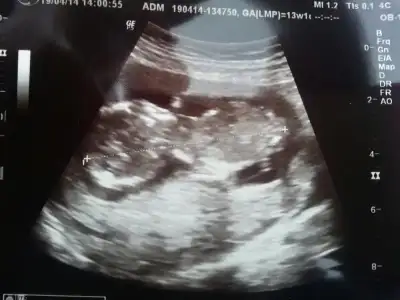

dr soylemeden siz gorun genital nub teorisi ( bebegin cinsiyeti)

$100_0199.webp Burda 12. haftamızı bitiriyoruz doktoromuz cinsiyetini görmüs ama heyecanlı olması için haftaya söyleyecek.öğrenince yazarım.

12+2 olduk bu gün teyzesi doktorumuz görmüs ama haftaya söyleyecekmis heyecanlı olsun diye :) ben ölüyorum meraktan haberi yok :))) siz tahminlerinizi yapın c.tesi kontrol sonucunu yazcam zaten.:emir_bebek: